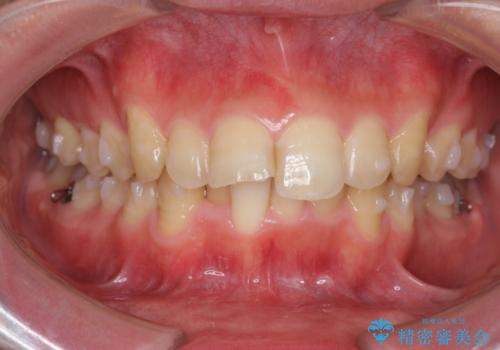

ガタつきの大きい前歯 インビザラインによるマウスピース矯正治療

- ガタつきの目立つ前歯の改善を求めて来院されました。

上顎前突、がたつきを改善すべく上顎臼歯の後方移動・ディスキングを行い歯並びの改善を計画します。

食事・歯ブラシ時以外の時間にしっかりとマウスピースを装着していただけたのでガタつきは大きく改善し良好な歯並びを得ることができました。